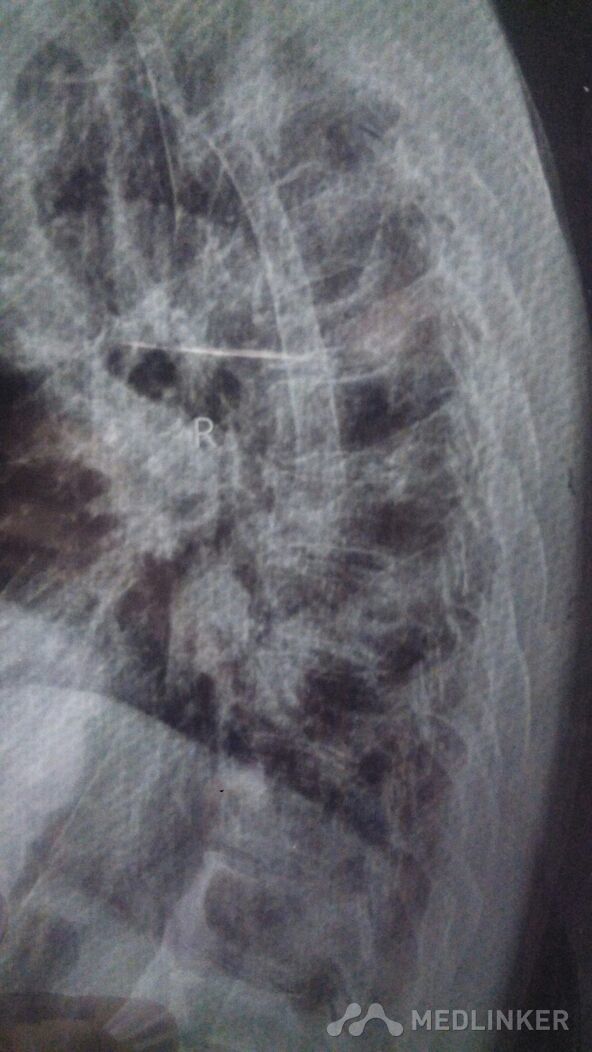

外科活动+胸椎体成形术。术后到术前很成形功。